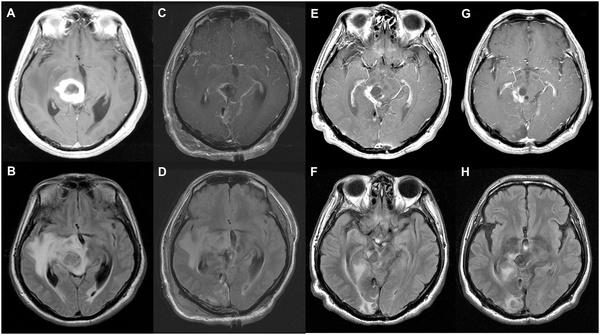

一名68岁男性因头痛和视力模糊入院。术前磁共振成像(MRI)显示外侧丘脑病变中的囊性和实性肿块,增强强化,提示胶质瘤。术后MRI显示肿瘤大体切除(C)、肿瘤次全切除(D)。在一年的随访MRI中,T1增强图像(E)中有不规则和模糊的增强,T2-FLAIR图像(F)中有高信号。在2年的随访MRI中,T1对比增强图像(G)和T2-FLAIR图像(H)处于稳定状态。患者健在,术后生存时间为1515天。